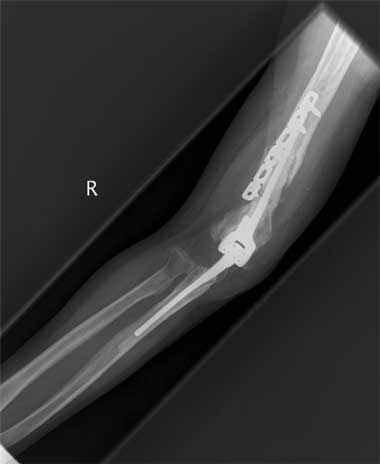

All 11 patients were taken to theatre within 24 hours of arrival at RPH and all underwent a washout and debridement. Depending on the injury, the procedures performed included open reduction and internal fixation; nerve, artery and tendon repair; and free flaps and split-skin grafting. Nine patients underwent multiple surgical procedures; 10 required open reduction and internal fixation with low contact dynamic compression plates for open fractures of the humerus, ulna and radius. The various plating procedures are illustrated in Box 2.

The most severe upper-arm injury involved Patient 7, with loss of the right distal humerus and olecranon, combined with an ulna nerve injury (Box 3). Initial treatment consisted of debridement and application of a bridging external fixator across the lost elbow joint (Box 4). This was complicated by iatrogenic radial nerve neuropraxia caused by the insertion of a Steinman pin. The external fixator was later replaced by a humeral allogeneic bone graft, an elbow prosthesis, and plate fixation of the humeral shaft (Box 5). The same patient also subsequently underwent a revision of the humeral plate procedure after a deep infection with Staphylococcus epidermidis was identified.

2 The various open reduction internal fixation (ORIF) procedures in patients with sideswipe injuries